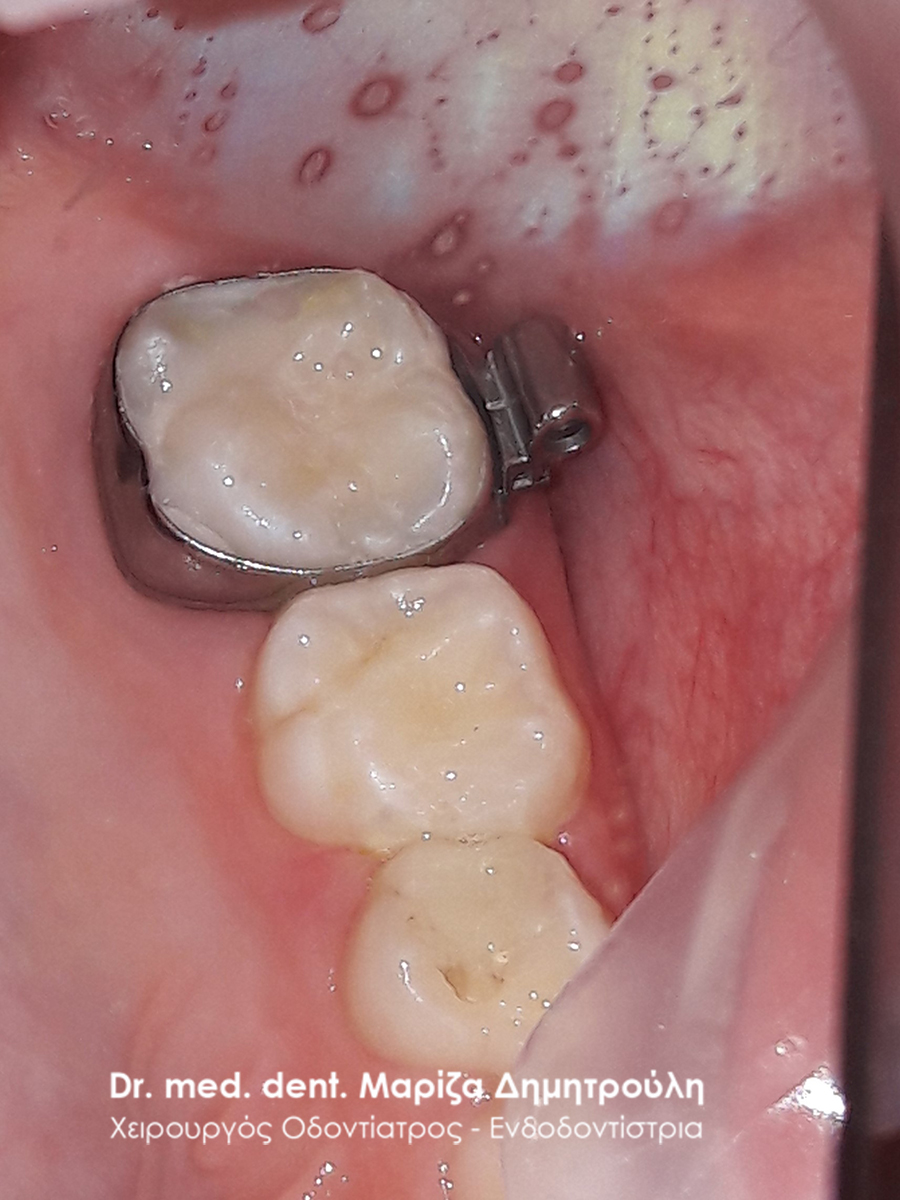

Dental filling of primary tooth

BEFORE

AFTER